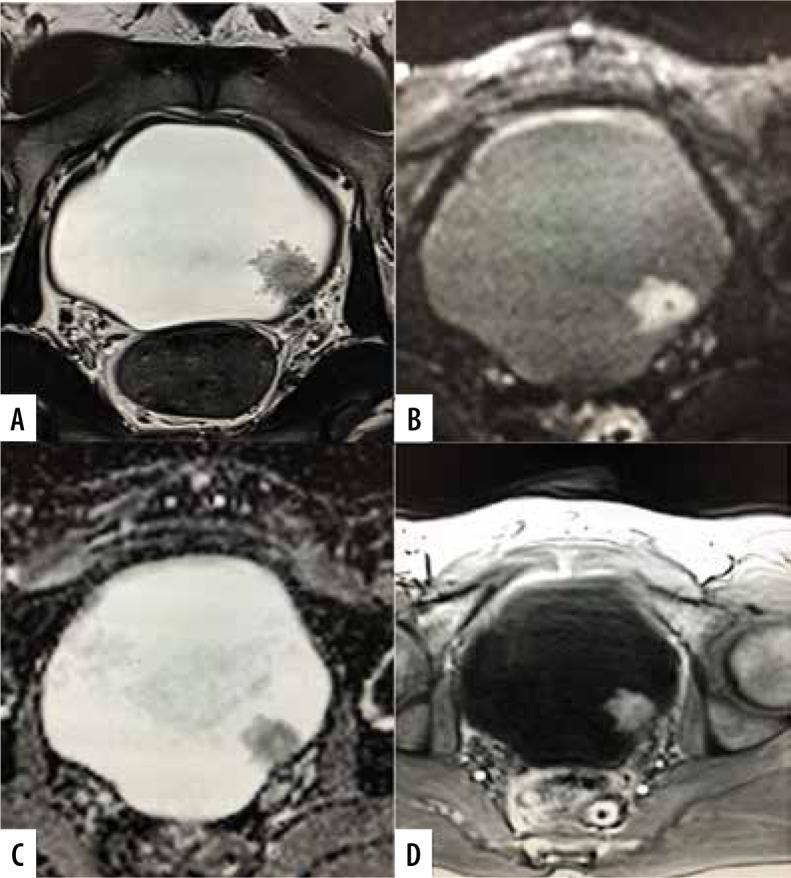

The purpose of the present study was to assess the diagnostic accuracy of the Vesical Imaging-Reporting and Data System (VI-RADS) scoring system in predicting muscle infiltration of bladder cancer (BC) on a pre-operative multiparametric magnetic resonance imaging (mpMRI).

The prospective study enrolled patients with bladder lesions detected on a preliminary ultrasonography or cystoscopy. The patients underwent mpMRI on a 3T MRI scanner followed by surgery within 2 weeks. The tumours were assigned a VI-RADS score by 2 experienced abdominal radiologists. The VI-RADS score was compared with postoperative histopathological findings to confirm detrusor muscle infiltration. The diagnostic performance of VI-RADS for predicting muscle invasion was assessed by calculating sensitivity, specificity, positive predictive value (PPV), negative predictive value (NPV) and accuracy.

A total of 60 patients were included in the study with a male: female ratio of 4.4 : 1. Transurethral resection of bladder tumour (TURBT) was performed in 47 (78.4%) and radical cystectomy in 13 (21.6%) patients. 19 (31.7%) had non-muscle invasive invasive BC (NMIBCa) and 41 (68.3%) had muscle invasive BC (MIBCa) on histopathology. There was a significant association between VI-RADS score and its components with muscle invasion ( < 0.05). A VI-RADS score of ≥ 3 had a sensitivity of 97.56% (95% CI: 0.87-0.99%), specificity of 73.68% (95% CI: 0.49-0.91), positive predictive value of 88.9% (95% CI: 0.79-0.94), negative predictive value of 93.33% (95% CI: 0.66-0.99), and diagnostic accuracy of 90% (95% CI: 0.80-0.96) for prediction of muscle invasion.

VI-RADS scoring system pre-operatively predicts the likelihood of muscle invasion in BC with a satisfactory diagnostic performance, and it should be incorporated in the diagnostic work-up of BC patients.